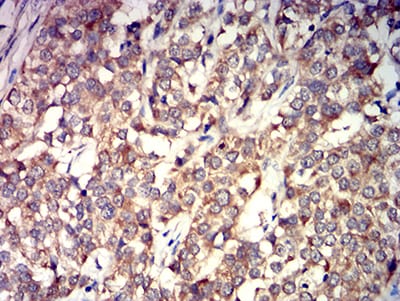

Immunohistochemical analysis of paraffin-embedded human cervical cancer tissues using GRIK4 mouse mAb with DAB staining.

Immunohistochemical analysis of paraffin-embedded human bladder cancer tissues using GRIK4 mouse mAb with DAB staining.